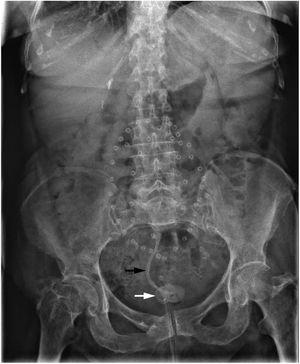

Mujer de 83 años, con neoplasia de endometrio tratada mediante histerectomía, doble anexectomía y braquiterapia, enteritis y cistopatía rádica, eventroplastia, colecistectomía, portadora de endoprótesis biliar plástica por coledocolitiasis (2009), no retirada por abandono del seguimiento, e infecciones de orina de repetición. Consulta por fecaluria y dolor abdominal. La radiografía muestra una imagen radiopaca alargada y otra redondeada en pelvis. La tomografía computarizada demuestra una cistolitiasis y una estructura tubular que comunica íleon y vejiga. Tras administración de contraste intravesical y llenado de íleon se demuestra una fístula enterovesical por migración de la endoprótesis. Se realiza resección intestinal y cistectomía parcial sin incidencias (figs. 1 y 2).